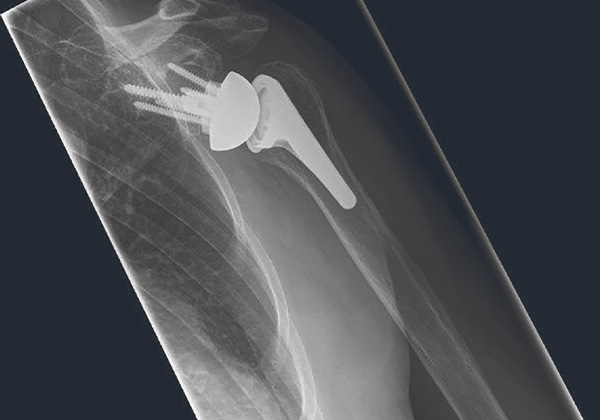

Ich kann auch wieder schwimmen gehen. Meine Schulter tat immer weh und ich konnte meinen Arm nicht mehr richtig einsetzen. Im Januar 2023 bin ich dann im Klinikum Rosenhöhe operiert worden. Jetzt nach der Rehabilitation geht es mir gut und ich habe keine Schmerzen mehr.“ 72-jährige Frau mit fortgeschrittenem Schultergelenksverschleiß auf der linken Seite. In der CT-Analyse des Gelenkes zeigte sich eine nach hinten gerichtete Dezentrierung des Oberarmkopfes.

Die Schultergelenkspfanne war bereits durch den Verschleißprozess deutlich asymmetrisch abgenutzt. Es wurde für die zentrierte Positionierung ein patientenspezifisches Instrument am 3D-Drucker angefertigt. Damit konnte während der Operation zielgenau gearbeitet werden und mit Hilfe eines speziellen defektausgleichenden Implantates das künstliche Gelenk aufgebaut werden. Durch dieses Vorgehen lassen sich haltbare und funktionell gute und sehr gute Ergebnisse für Patient*innen erzielen.